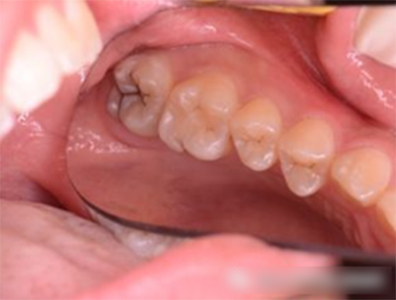

第二恒磨牙也有深的窩溝點(diǎn)隙